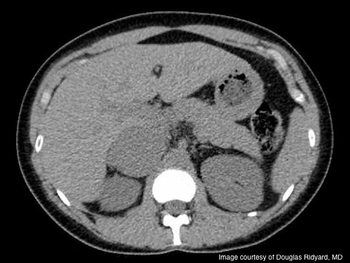

Contrast-enhanced ultrasound for detecting renal cell carcinoma recurrence following ablation and new protocols for low-dose computed tomography in stone patients were among the other research highlights in imaging at the AUA annual meeting.